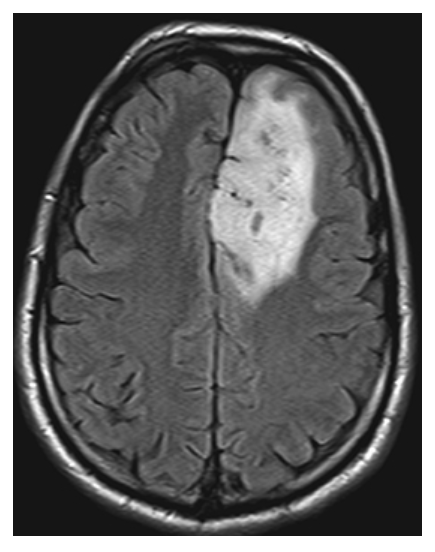

Brain Metastasis. Axial T2W image shows the left parietal mass with high central signal likely due to necrosis and high signal in the surrounding white matter due to vasogenic edema.